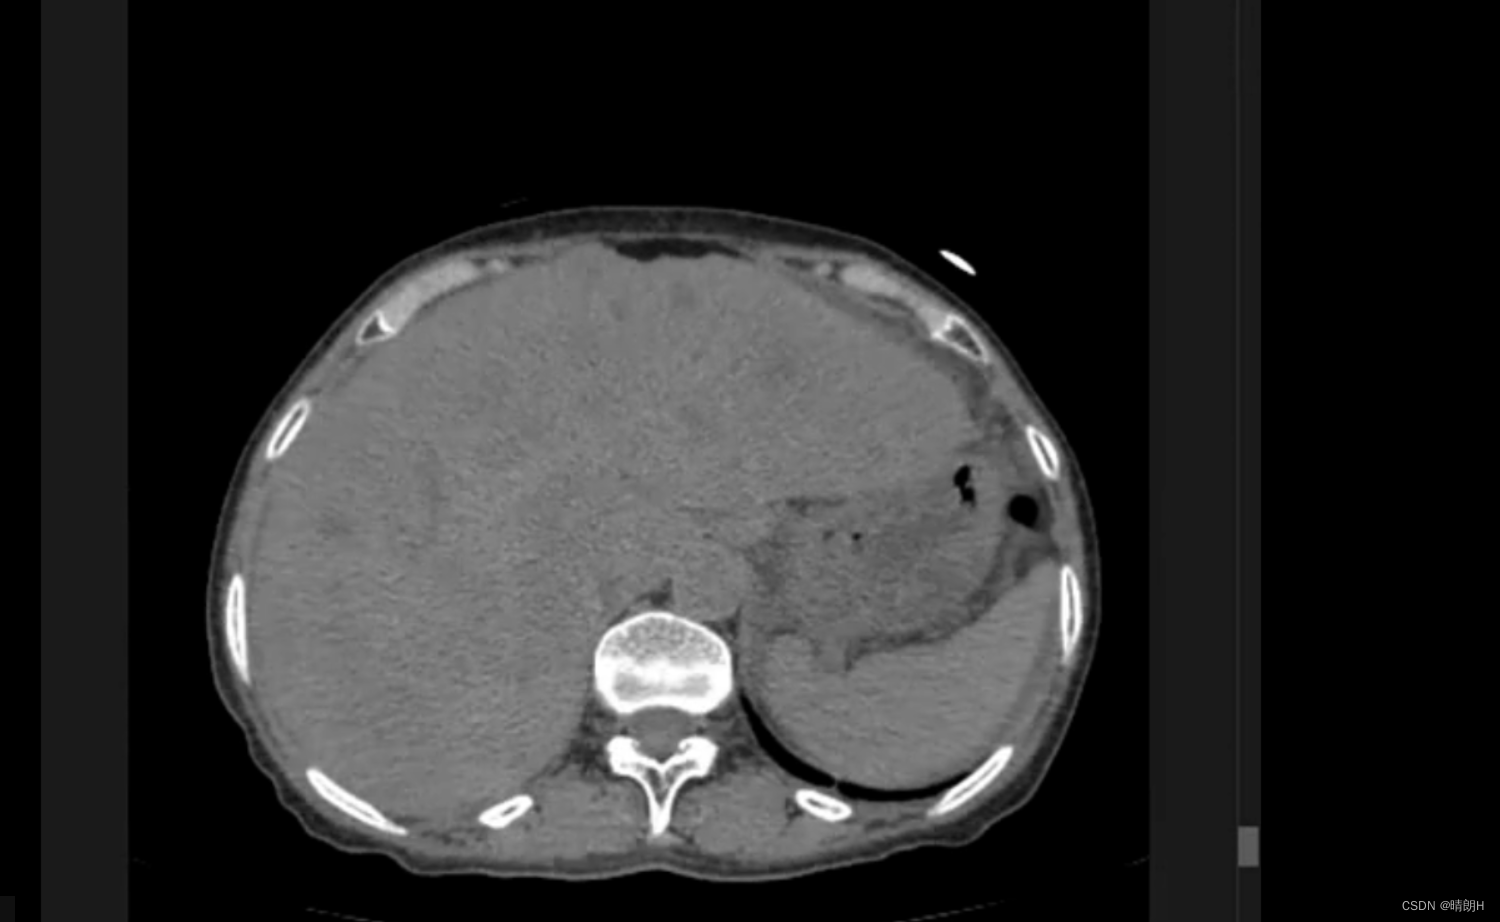

除大量图像外,图像信息是所有焦点! 看看肺部这一个开始是黑色的,似乎没什么,做窗口宽的窗口位置操作,它看起来像一个清晰的肺部纹理!